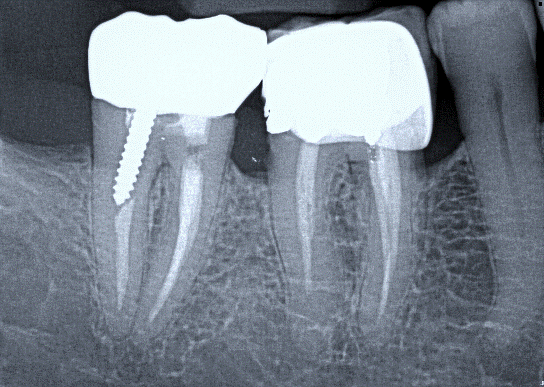

2. (Select ONE OR MORE correct answers)

What observation(s) can be made for tooth 4.7?